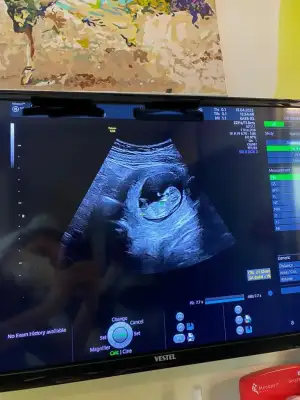

şaşkınlığımdan ultrason fotoğrafını yolda düşürmüşüm bulamadık ama videodan ekran görüntüsü aldım bi yorumlarsanız çok sevinirim

doktor kanama alanı yok kese çok güzel kalbi de iyi atıyor hiç bir sorun yok lekelneme de rahimden kaynaklı değil dedi fitili değiştirdi ağızdan alınan başka bir progestan verdi 11. Haftada gel dedi içim Cook rahtladi inşallah sağlıklı bir şekilde de ilerler

(karından ultrason)